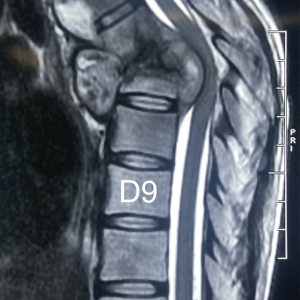

Photo Gallery